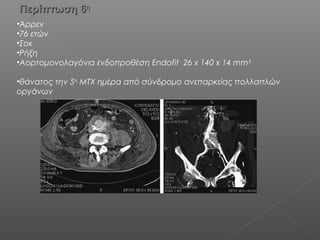

Περίπτωση 6Περίπτωση 6ηη

•Άρρεν

•76 ετών

•Σοκ

•Ρήξη

•Αορτομονολαγόνια ενδοπροθέση Endofit 26 x 140 x 14 mm3

•θάνατος την 5η

ΜΤΧ ημέρα από σύνδρομο ανεπαρκείας πολλαπλών

οργάνων